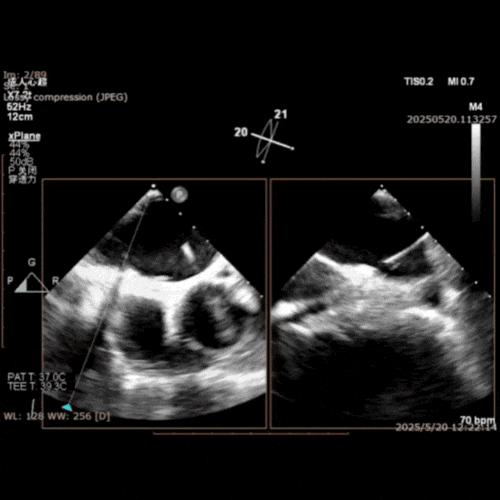

在经股静脉途径的TEER手术时,房间隔穿刺是一个很重要的基础步骤。有时候房间隔组织较韧较厚(多见于房间隔短穿刺位置需要靠后,或者外科房间隔修补术后),穿刺针通过之后要通过导引大鞘(GC)存在着较大困难,若强行推送大鞘可引起房间隔撕裂到左心房顶引起灾难性心包填塞。传统做法时使用外周球囊对房间隔进行扩张,但是不是每个导管室都常规配备外周球囊,且使用过大球囊仍可引起房间隔撕裂风险。我们提供了一种更简洁的方式,即使用导引鞘内芯和房间隔穿刺鞘两个管子(双管齐下)同时扩张房间隔穿刺口,再推送导引大鞘通过房间隔,无需额外器械,操作简单高效且安全(图1-4)。

图1. 房间隔穿刺处肥厚,GC难以通过房间隔